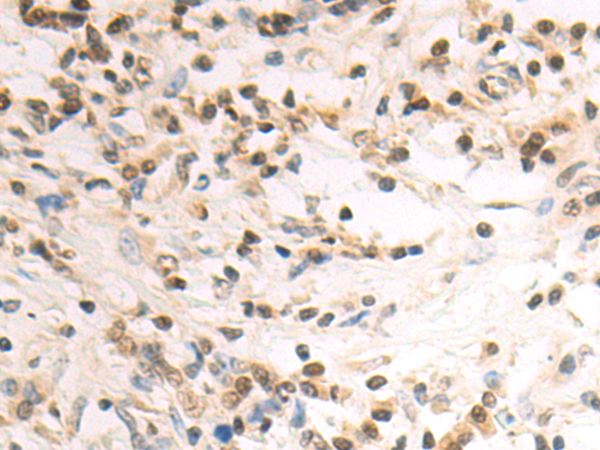

分类: 科研抗体货号: P09826别名: PRL3; PRL-3; PRL-R应用: IHC反应种属: Human